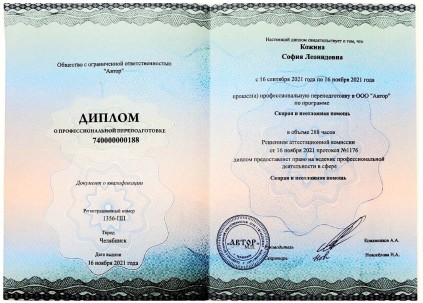

Сертификаты